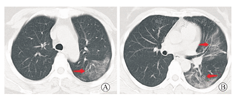

入院后予磷酸奥司他韦胶囊(75 mg/次,2次/d)抗流感病毒,莫西沙星片(0.4g/次,1次/d)抗感染及相关祛痰止咳等对症治疗。患者仍有反复发热,体温为37.3~38.9 ℃。因患者存在新型冠状病毒肺炎(COVID-19)流行病学史,于1月22日送检咽拭子及血清,经金华市及浙江省疾病预防控制中心检测,确认2019-nCoV核酸阳性,确诊为COVID-19。加用干扰素α-2b针雾化吸入(500万U,2次/d);洛匹那韦/利托那韦片(2片/次,1次/12 h)口服;同时予中药辅助治疗,体温恢复正常。1月28日患者再次出现发热,体温最高37.8 ℃,无明显咳嗽、咳痰,无胸闷气急,无气喘。复查床边胸片提示左肺感染,较1月21日病灶进展。复查血常规:白细胞7.8×109/L,嗜中性粒细胞占比0.796,淋巴细胞占比0.132,超敏CRP 20.8 mg/L;血降钙素原0.041 ng/mL;复查咽拭子2019-nCoV核酸阳性;予上述药物继续抗病毒及抗感染,加用甲泼尼龙琥珀酸钠针(40 mg,1次/d)静脉滴注,共用3 d。1月29日,患者体温恢复正常,无咳嗽、咳痰,无胸闷气喘,自觉症状较前好转,食欲好转。1月30日停用甲泼尼龙琥珀酸钠针,其他治疗同前。1月31日,患者体温持续正常,无明显不适。复查胸部CT,示左肺及右肺下叶片状高密度影,边缘模糊,右肺下叶膨胀不全(图2)。2月3日,复查胸部CT,炎症范围较1月31日有所吸收(图3)。复查血常规:白细胞6.74×109/L,嗜中性粒细胞占比0.76,淋巴细胞占比0.165,超敏CRP 1.0 mg/L,血降钙素原0.04 ng/mL。2月3日和4日复查咽拭子2019-nCoV核酸,检测均阴性,达到出院标准,予2月5日出院。

注:箭头所示为病灶吸收好转